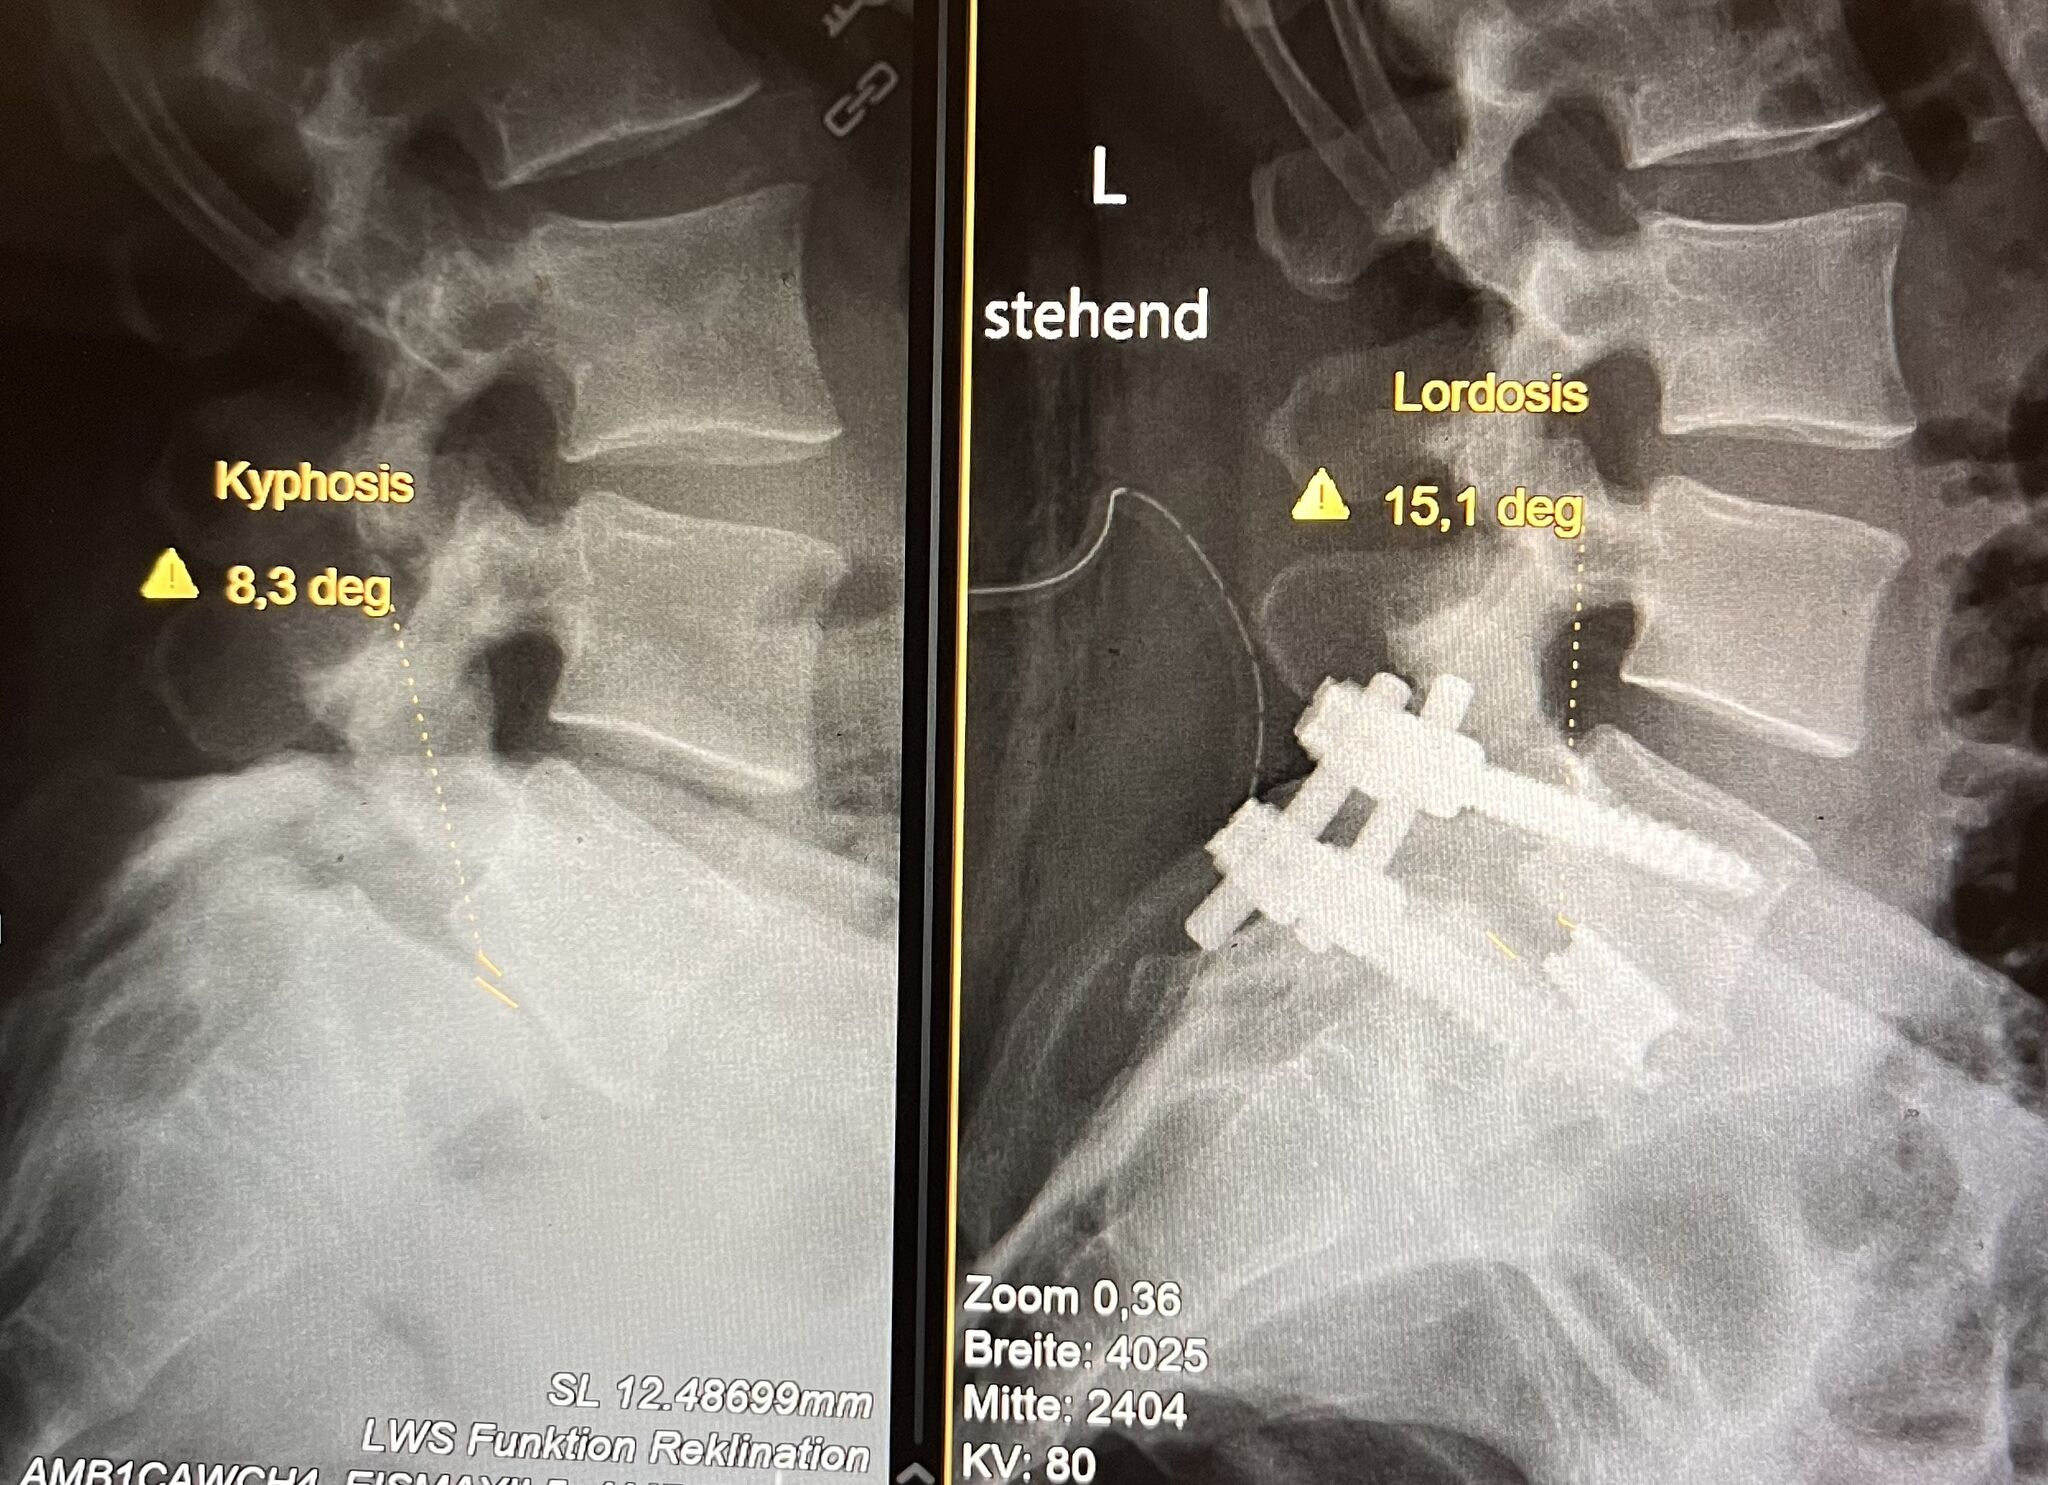

• Scoliosis (spinal curvature)

• Kyphosis

• X-rays to evaluate bone structure and alignment

• CT scans to examine spinal abnormalities